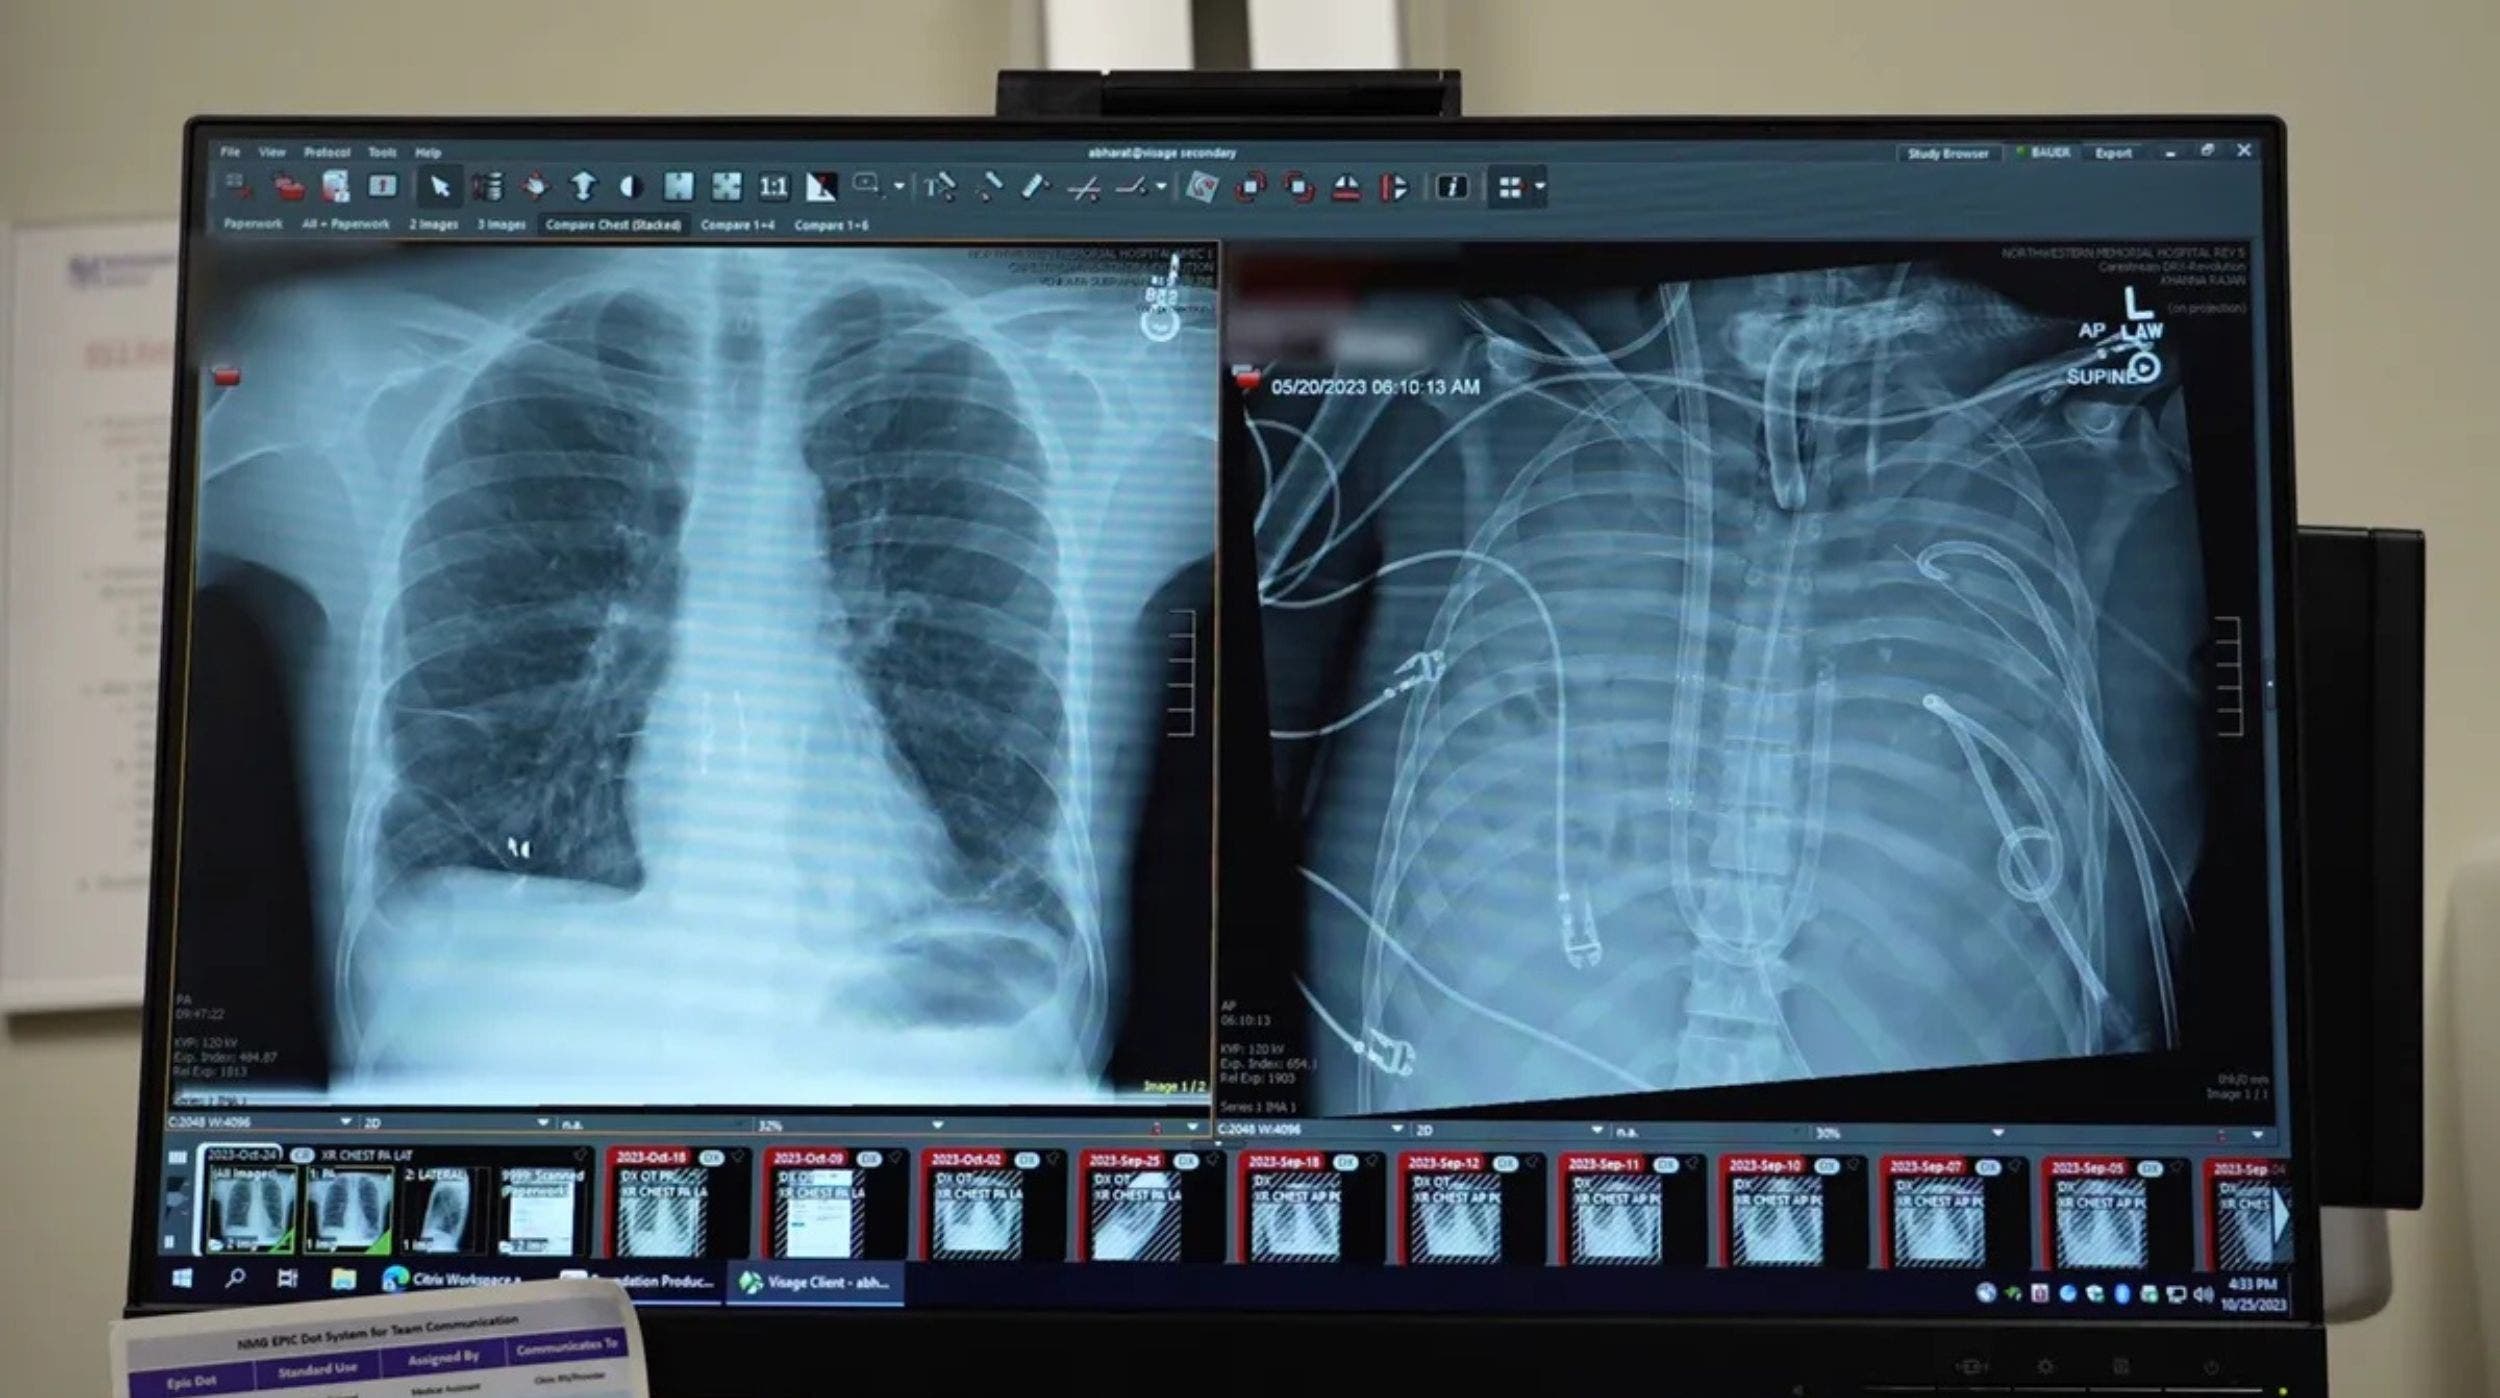

El hombre, de 33 años, llegó al hospital con un síndrome de distrés respiratorio agudo provocado por una infección grave que había causado daño irreversible en ambos pulmones. Ante la falta de opciones, un equipo de cirujanos de la Universidad Northwestern, liderado por el Dr. Ankit Bharat, decidió retirar los pulmones dañados y conectar al paciente a un dispositivo que oxigenaba su sangre y mantenía estable la circulación, en lo que se ha descrito como un verdadero puente vital hacia la cirugía de trasplante.

Más allá de su impresionante supervivencia, el caso representa un hito científico: es una de las primeras veces que se demuestra que un sistema artificial puede reemplazar temporalmente por completo la función pulmonar humana mientras se espera un donante compatible. El análisis molecular de los pulmones extraídos reveló que el daño era tan severo que no podría haberse recuperado por sí solo sin un trasplante — algo que aporta datos valiosos para futuras terapias en casos de falla pulmonar aguda.

Dos días después de la neumonectomía bilateral, el paciente recibió un trasplante doble de pulmón y, con el paso del tiempo, ha recuperado una función respiratoria saludable, permitiéndole retomar su vida cotidiana. Esta hazaña médica abre la puerta a nuevas estrategias para mantener con vida a pacientes críticos mientras esperan órganos disponibles, especialmente en contextos donde la disponibilidad de donantes es limitada.